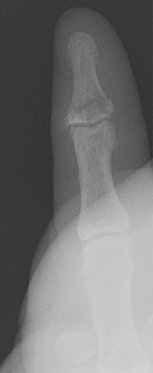

Return to Phalangeal Fracture (Hand)